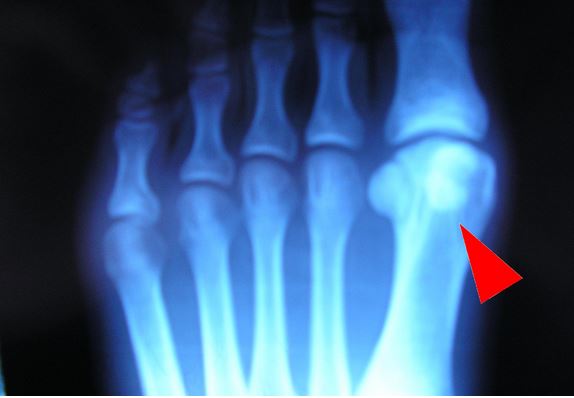

Les sésamoïdes du gros orteil, sont deux os de petite taille situés sous la tête du premier métatarsien, le sésamoïde externe rarement touché et le sésamoïde interne, le plus gros (12 sur 10 mm) et le plus exposé, directement situé sous la tête du premier métatarsien. Ils sont constants, et de la taille d'un petit haricot, et recouverts de cartilage sur leur face supérieure. Ils donnent attache à de nombreux ligaments et stabilisent le tendon fléchisseur de l'orteil. Leur rôle est de transmettre le poids du corps lors de l'impact du pied au sol. Le sésamoïde interne subit plus de poids que l'externe. Lors d'une course rapide (sprint), le sésamoïde interne supporte l'équivalent de 4 fois le poids du corps. Un pied creux constitue un élément favorisant de fracture. Leur atrophie ou leur absence est exceptionnelle.

Le diagnostic de certitude est fait sur les radiographies (bien dégager le sésamoïde suspect par des incidences multiples et faire des clichés comparatifs des 2 avants pieds) qui visualisent l'écartement des 2 fragments dont les bords sont irréguliers (fracture en traction).

fracture du sésamoïde latéral

Diagnostic différentiel avec un sésamoïde bipartita dont les bords sont réguliers et dont la somme des 2 fragments donne un sésamoïde de taille bien supérieure à un sésamoïde normal, ce qui n’est pas vrai si l'on additionne les deux fragments d’un os fracturé.

Sésamoïde bipartita